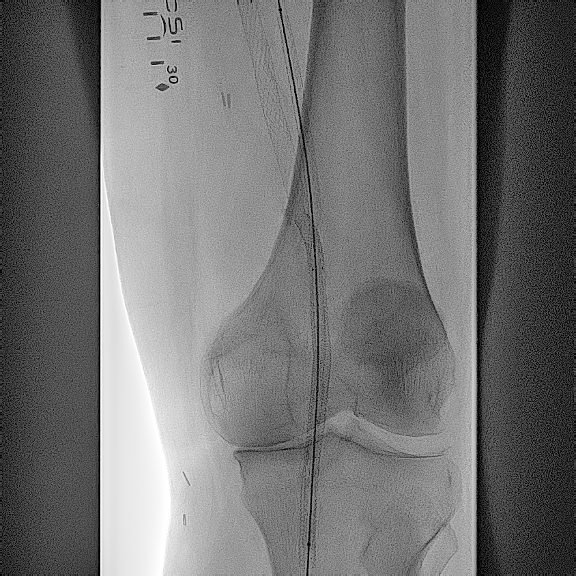

After gaining access into the SFA, the first step of crossing from the SFA into the femoral vein was done with the Endocross catheter (Endologix; Figure 5). Although it had to be done through stent struts, this proved to be fairly easily accomplished with minimal resistance. A 0.014-in Grand Slam wire (Asahi Intecc Medical) was snared from the Endocross to the femoral vein using a pre-existing snare. The crossover site was then dilated using a 5.0-mm Serranator balloon (Cagent Vascular; Figure 6), allowing for the Endocross to advance into the distal femoral vein for distal access into the P1 portion of the popliteal artery through a pre-existing Supera stent (Abbott Cardiovascular) with minimal resistance. This was pre-dilated with a 4.0-mm Coyote balloon (Boston Scientific) followed by a 5.0-mm Serranator balloon (Figure 7). After sufficient pre-dilatation, the Torus stents (Endologix) were placed from the distal anastomosis to proximal anastomosis (5.5 mm distally and 6.5 mm proximally; Figure 8) followed by post-dilatation with a 6.0-mm Mustang balloon (Boston Scientific; Figure 9). Repeat angiographic assessment showed good apposition and expansion of the stents and robust vessel runoff down to the foot (Figure 10). The patient’s wound did require transmetatarsal amputation but was spared an above-knee amputation. His wounds had shown sufficient healing 3 months from the principal procedure.